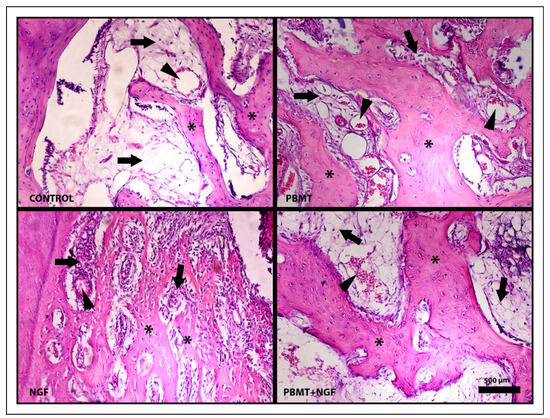

Histopathological Findings of Bone Tissue